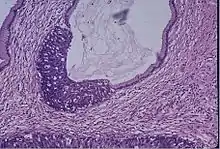

Microscope image of the cervical gland showing an area of high grade epithelial dysplasia.

Cervical screening by the Pap test or other methods is highly effective at detecting and preventing cervical cancer, although there is a serious risk of overtreatment in young women up to the age of 20 or beyond, who are prone to have many abnormal cells which clear up naturally.[26] There is a considerable range in the recommended age at which to begin screening around the world. According to the 2010 European guidelines for cervical cancer screening, the age at which to commence screening ranges between 20 and 30 years of age, "but preferentially not before age 25 or 30 years", depending on the burden of the disease in the population and the available resources.[27]